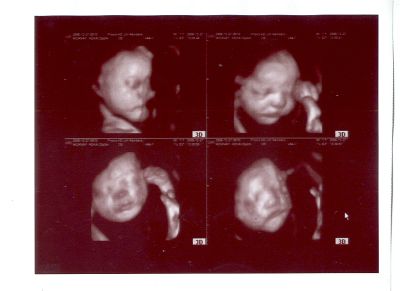

Végre sikerült eljutni 4D-re... majdnem megint le kellett mondani, mert Zsuzsa az egész ünnepeket végigbetegeskedte, még most sincs rendben szegény. :( Egyik komplikációból a másikba esik, ma is lázas volt, anyukám vigyázott rá, aztán szépen ő is belázasodott. :?

Szilvi baba jóóóó nagy, 2 kg-ra saccolta a szonográfus, és a legtöbb mérete egy-két héttel "idősebb" illetve nagyobb mint a kora. Hát Zsuzsával is ez volt, ő is jó nagy baba lett. Ami egy picit aggasztó, hogy több magzatvizet is látott a szonográfus, de hát ez lehet a cukrom miatt is, holnap megyek orvoshoz, megkérdem.

Jaj, és a legfontosabb majdnem lemaradt, a sztárfotó Szilviről! :)

Kép